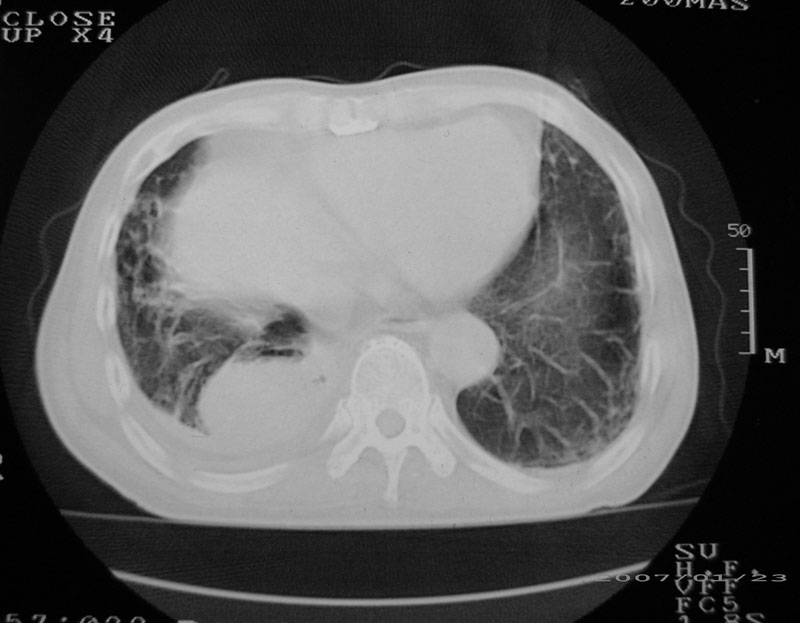

以下是引用天南地北在2007-1-24 18:00:00的发言:[br]1:右下肺内基底段类椭圆性肿快影:考虑1:右下球形肺炎2:右下肺隔离症,建议抗炎治疗后复查。[br]2:右肺及左下肺感染,右侧少量胸腔积液。